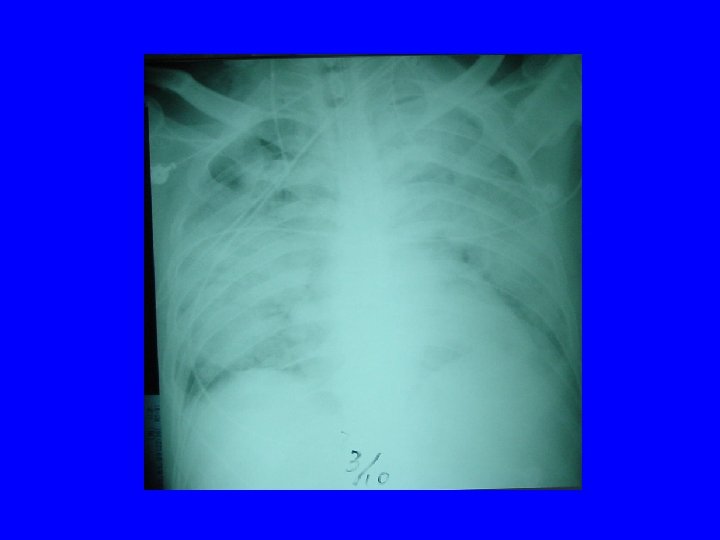

Radiology of typical case Lee NEJM 4/7/04

Radiographic Features of SARS • Infiltrates present on chest radiographs in > 80% of cases • Infiltrates – initially focal in 50 -75% – interstitial – Most progress to involve multiple lobes, bilateral involvement

Lee N. et al NEJM 4/7/03